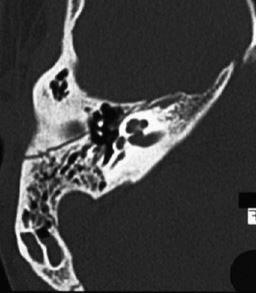

Question 10 - Vous réalisez un scanner des rochers. Voici l’image du rocher droit. Qu’en dites-vous ? Figure 11

Une fracture longitudinale est dans l’axe du rocher, de la base en avant à la pointe en arrière. C’est le cas ici

Ce n’est pas le cas ici (cf. commentaire général)

Ici, toute la zone visible intracrânienne est grise. Une bulle d’air se voit très facilement et se présente comme un rond noir (de l’air). Cela traduit une brèche ostéoméningée

L’oreille moyenne correspond à la partie externe du rocher. C’est la cavité où se trouvent les osselets qui est normalement remplie d’air. Elle doit donc être noire sur le scanner (elle est ici partiellement remplie de liquide en gris)

La mastoïde se trouve en arrière de l’oreille moyenne et est constituée de plusieurs cellules aériennes (donc noires sur le scanner). Ici, de nombreuses cellules sont grises, donc liquidiennes

Voici un schéma rappel des deux principales fractures du rocher. La fracture longitudinale est le plus fréquente et la moins grave, puisqu’elle respecte le plus souvent l’oreille interne et le nerf facial. Elle peut tout de même entraîner une surdité de perception par commotion ou rarement une cophose si le trait de fracture passe par la cochlée. La fracture transversale est le plus souvent grave car elle passe beaucoup plus souvent par la cochlée avec un risque important de cophose. Figure 12